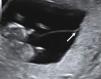

Fetal gender The identification of discordant fetal gender indicates dichorionic twinning (Fig. 6). The positive predictive value of discordant gender (when correctly identified) is 100%. However, considering that around 50% of concordant sex twins are dichorionic, the definition of chorionicity needs further sonographic signs.